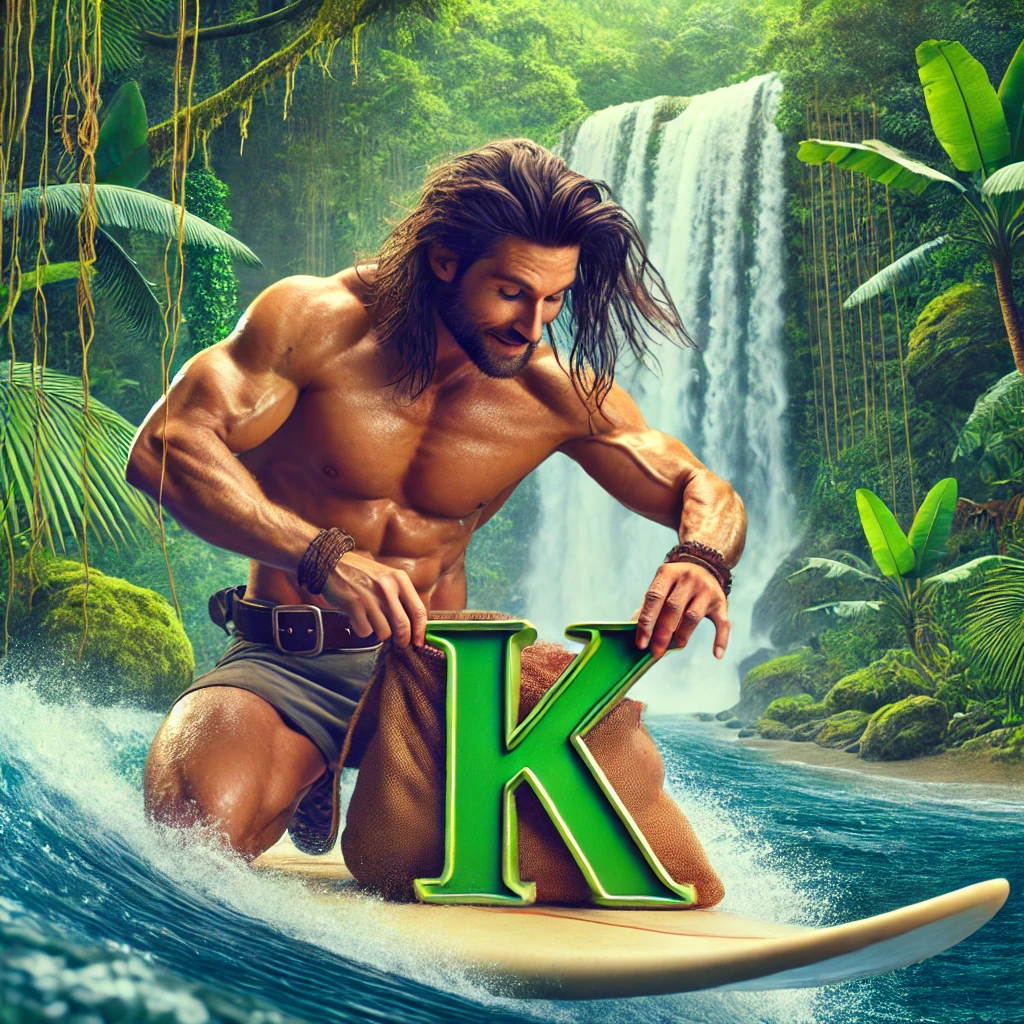

Beispiele für lustige Merkbilder:

Dank der Bilderstellung durch künstliche Intelligenz (zum Beispiel mit ChatGPT) lassen sich schnell eingängige Bilder erstellen. Wenn deine Fantasie bereits eine Vorstellung hat, wie du dir etwas gut merken könntest, lasse dazu ein passendes Bild generieren:

- Hydrochlorothiazid (ein Medikament) senkt Kalium im Blut. In Hydrochlorothiazid steckt ungefähr das Wort Tarzan – daher nutze ich ein KI-generiertes Bild, wie Tarzan Kalium (K) in einen Beutel gibt (es stiehlt), daher sinkt es: